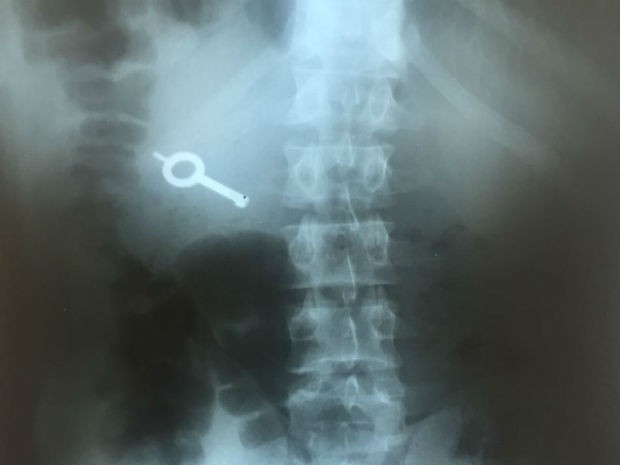

Um dos presidiários envolvidos em uma rebelião na 13ª Subdivisão Policial de (SDP) de Ponta Grossa, na região dos Campos Gerais do Paraná, na noite de domingo (11) foi detido. Durante a rebelião os presos rasgaram as froupas de um funcionário e tomaram o molho de chaves. A chave foi localizada após o preso passar por um detector de metais.

O detento foi internado até que venha a expelir o objeto.